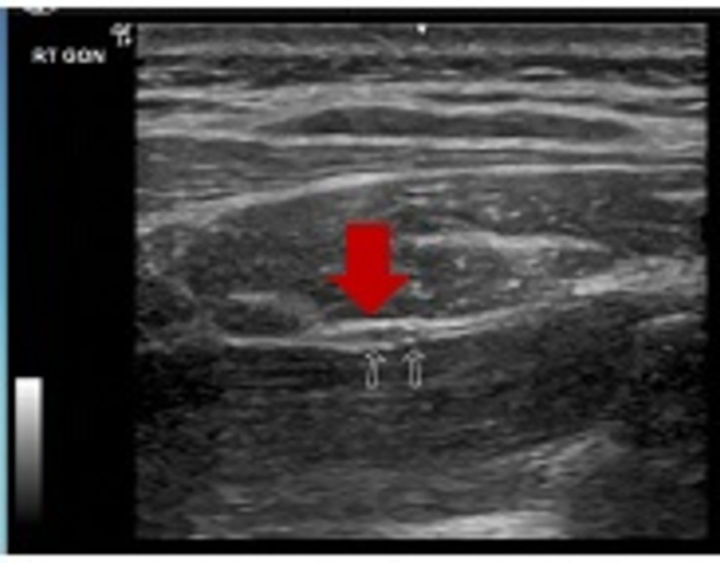

如果和此病人一样,曾尝试保守治疗,但效果不佳,且疼痛点是两侧“枕神经”路径上易产生压迫或沾黏的位置,近年来国外医疗发展的“超音波引导神经解套注射治疗(Nerve Hydrodissection) ”是不错的选项;不过须格外注意,若病人有外伤病史、伴随神经肌肉萎缩或保守治疗无效,可能为颈部脊髓压迫或是颈椎不稳定的情况,须转介神经外科医师评估其它可能性,或採取其它治疗。

(超音波引导神经解套注射治疗,增加治疗效果及准确性)